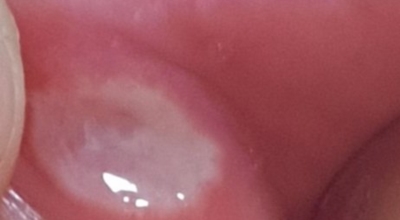

입안에 우유 이물질 같은 흰 막이 생기고 통증이 있으면, 구강 칸디다증을 의심할 수 있답니다. 구강 칸디다증은 '아구창'이라고 부르기도 하고, 입안에 우유 순수하지 않은 물질 같은 흰 막이 생기면서 음식을 삼킬 때 통증을 동반해요.구강 칸디다증을 일으키는 칸디다는 사람의 입, 소화기관, 질, 피부에 정상적으로 살고 있는 진균인데, 면역기능이 정상인 사람에게는 아무런 이상을 유발하지 않아요.

그렇지만, 면역기능이 떨어지게 되면 칸디다증을 일으킬 수 있어요. 특히 당뇨병, 결핵, 혈액질환, 면역질환, 악성종양을 지니고 있거나, 노약자, 어린 아이, 임산부 등 체력이나 면역력이 떨어져 있는 사람들, 틀니를 활용하던가, 구강 건조증이 있는 사람, 항생제를 장기 먹는 사람에게 생기기 쉬워요.